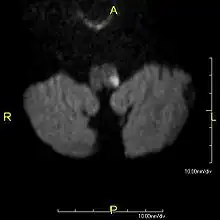

Clinical B1000 diffusion weighted MRI image showing an acute left sided dorsal lateral medullary infarct -